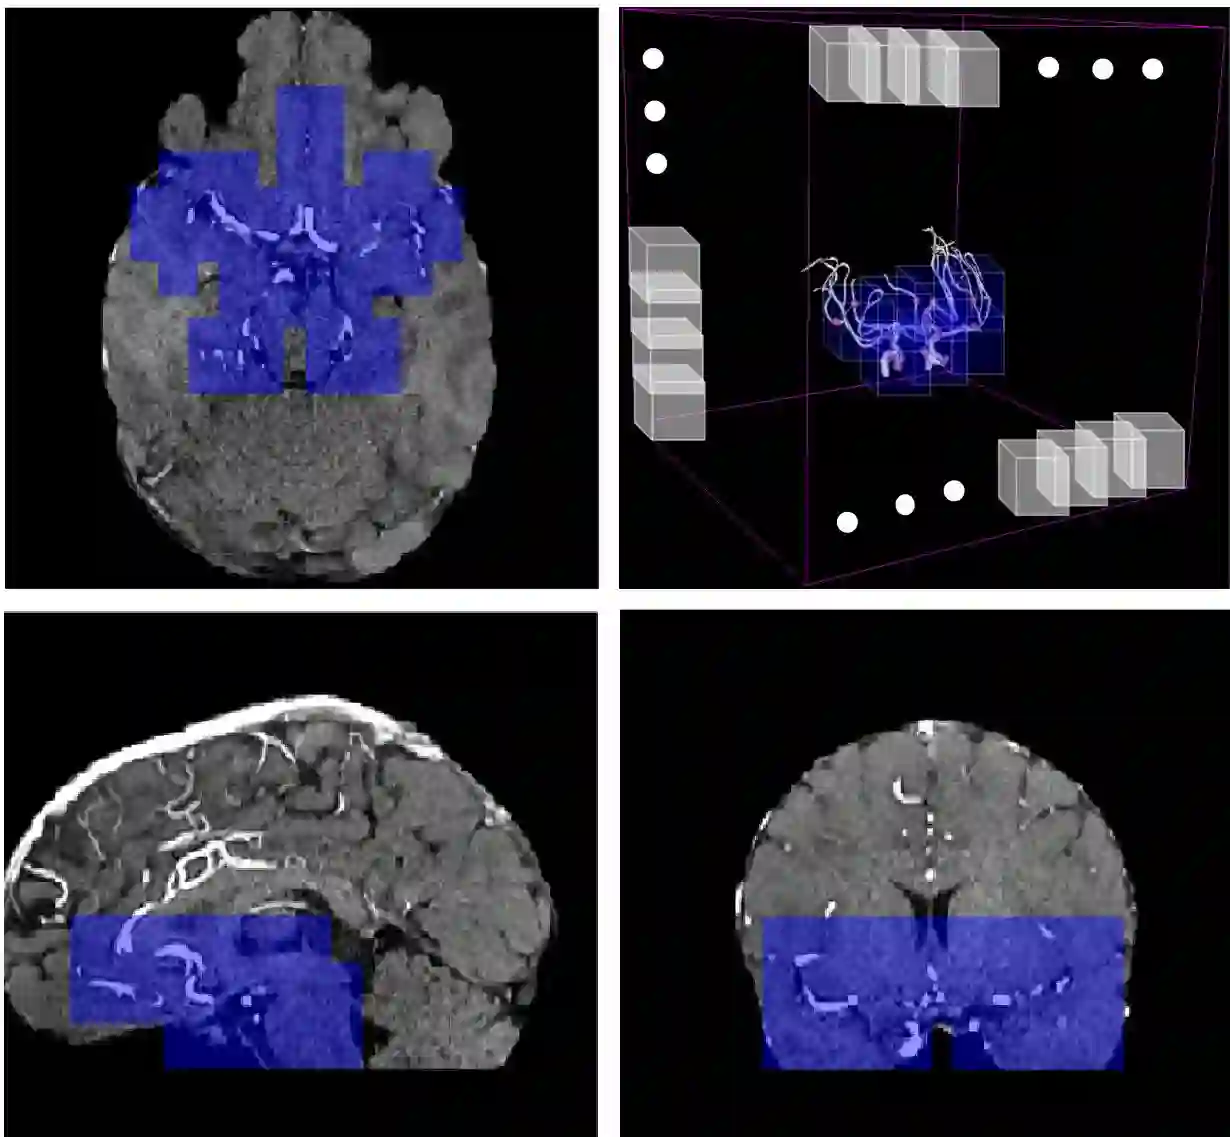

Supervised segmentation algorithms yield state-of-the-art results for automated anomaly detection. However, these models require voxel-wise labels which are time-consuming to draw for medical experts. An interesting alternative to voxel-wise annotations is the use of weak labels: these can be coarse or oversized annotations that are less precise, but considerably faster to create. In this work, we address the task of brain aneurysm detection by developing a fully automated, deep neural network that is trained utilizing oversized weak labels. Furthermore, since aneurysms mainly occur in specific anatomical locations, we build our model leveraging the underlying anatomy of the brain vasculature both during training and inference. We apply our model to 250 subjects (120 patients, 130 controls) who underwent Time-Of-Flight Magnetic Resonance Angiography (TOF-MRA) and presented a total of 154 aneurysms. To assess the robustness of the algorithm, we participated in a MICCAI challenge for TOF-MRA data (93 patients, 20 controls, 125 aneurysms) which allowed us to obtain results also for subjects coming from a different institution. Our network achieves an average sensitivity of 77% on our in-house data, with a mean False Positive (FP) rate of 0.72 per patient. Instead, on the challenge data, we attain a sensitivity of 59% with a mean FP rate of 1.18, ranking in 7th/14 position for detection and in 4th/11 for segmentation on the open leaderboard. When computing detection performances with respect to aneurysms' risk of rupture, we found no statistical difference between two risk groups (p = 0.12), although the sensitivity for dangerous aneurysms was higher (78%). Our approach suggests that clinically useful sensitivity can be achieved using weak labels and exploiting prior anatomical knowledge; this expands the feasibility of deep learning studies to hospitals that have limited time and data.